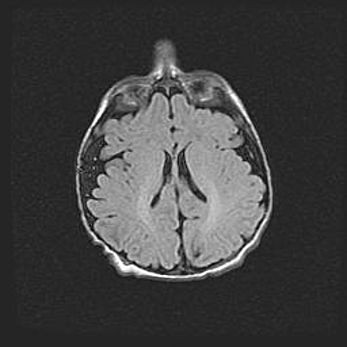

Сообщающаяся гидроцефалия. Кистозная энцефаломаляция головного мозга.

Возраст: 3 месяца 4 дня

Вес: 3100 г

Пол: женский

Окружность головы: 34 см

Срок гестации: 31 неделя

Кистозная энцефаломаляция головного мозга - одна из форм поражения головного мозга в детском возрасте. Характеризуется возникновением множественных и распространённых кист в коре, белом веществе и подкорковых образованиях головного мозга у плодов, новорождённых и детей раннего возраста. Развитие кистозной энцефаломаляции связано с внутриутробной асфиксией и гипотонией, родовой травмой, тромбозом синусов, пороками развития сосудов, инфекциями, сепсисом и другими причинами. Наиболее значимые инфекционные агенты: вирусы простого герпеса, цитомегалии, краснухи, токсоплазмы, энтеробактерии, золотистый стафилококк и другие.